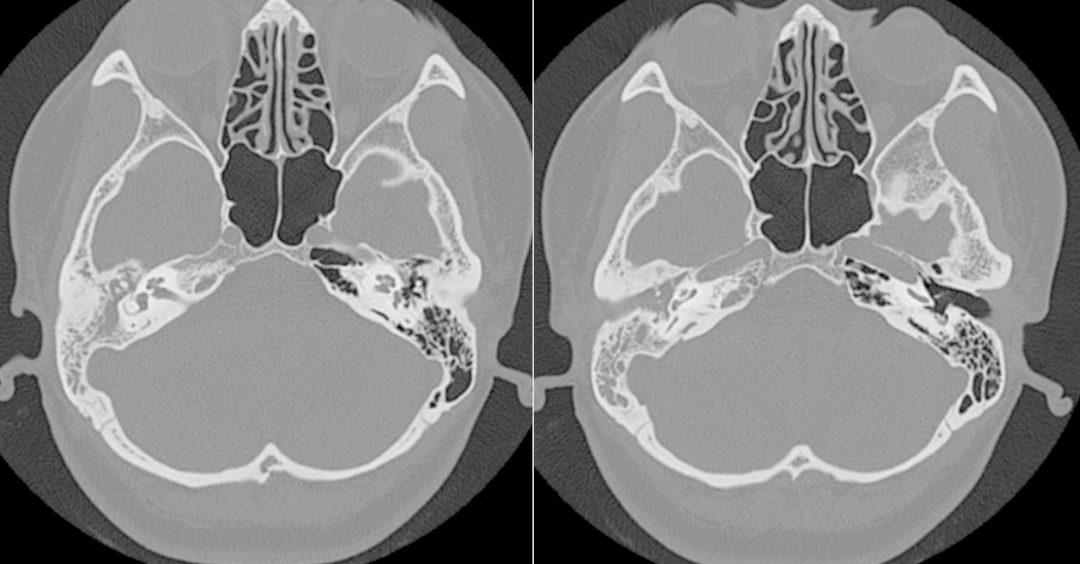

术前CT

由于患者属于二次手术,正常的解剖结构遭到了破坏、长期的炎症病变使术区不断渗血且粘连明显极大地加大了手术难度。在团队的配合下,张晓彤教授凭借着高超的医术克服手术中的重重困难,经过近4小时的紧张奋战,手术顺利完成。术后,在医护人员的精心照料下,李女士恢复良好。